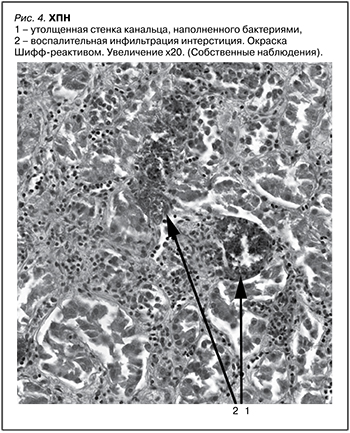

У 18 (63,3%) пациентов с изолированным мочевым синдромом на фоне ХПН в нефробипотатах обнаружено значительное утолщение стенок канальцев с большим скоплением бактерий в просвете и лимфоцитарно-лейкоцитарной инфильтрацией окружающего интерстиция (рис. 4).

Проведенное в рамках настоящей работы исследование показало, что уровень утренней гликемии и процентное содержание эритроцитов с HbA1c у здоровых людей и пациентов с ХПН не имели статистических различий. При этом нарастающая по интенсивности недиабетическая глюкозурия совпадала со статистически значимым увеличением клеточных и бактериальных включений мочевого осадка. В отличие от транзиторной канальцевой гематурии токсического генеза у пациентов с изолированным мочевым синдромом на фоне ХПН в нефробиоптах наряду с неизмененными кровяными тельцами в просвете дистальных канальцев наблюдалась фиксация выщелоченных эритроцитов и продуктов их деградации. Использование специальной окраски позволило в 36,7% наблюдений визуализировать ШИК-позитивные белковые цилиндры в просвете канальцев с выраженной атрофией их эпителия, и в 63,3% случаев имело место значительное утолщение стенок канальцев с большим скоплением в их просвете бактерий и лимфоцитарно-лейкоцитарной инфильтрацией окружающего интерстиция.